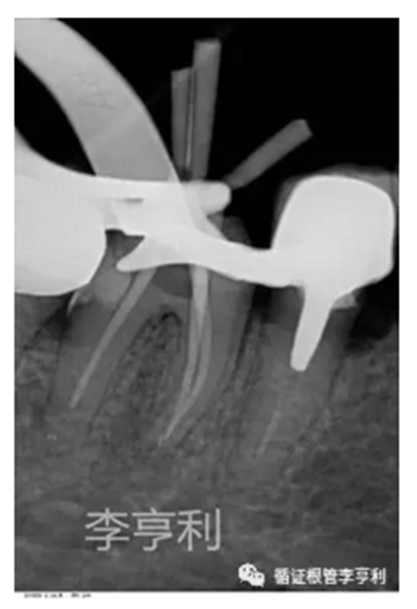

暴露器械斷端 (2017-06-26)

器械被超聲震出 (2017-06-26)

分離器械約為4mm長 (2017-06-26)

【治療過程】:由于患者根管系統(tǒng)較細窄,無法建立旁路疏通MB根,因此決定取出分離的器械。首先在顯微鏡下暴露器械斷端,然后使用超聲工作尖震動斷針,30分鐘內斷針被順利震出,然后疏通MB到根尖。之后就常規(guī)完成剩余根管治療步驟,轉回進行后續(xù)冠修復。

超聲震蕩方法的優(yōu)勢在于效率最高,且無需特殊的器械設備。一般用于斷械長度在4.5mm以內,其所需時間一般為60min以內,否則取出的可能性會隨著時間遞增而迅速下降;

注意保護其余根管口,避免取出斷針時掉落于其他的根管內;

使用超聲工作尖的時候,一定要注意保護根管壁,避免發(fā)生側穿或過度削弱牙根抗力;